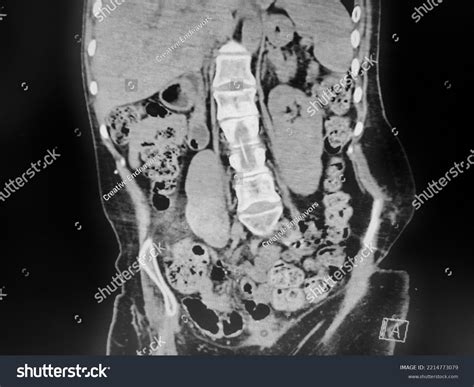

Diagnosing Constipation with X-Ray

An X-ray is a common diagnostic tool used to visualize the internal structures of the body. When it comes to constipation, an abdominal X-ray can provide valuable information about the state of the colon and the presence of fecal matter. This imaging technique is particularly useful in cases where the cause of constipation is not immediately apparent.

Interpreting Constipation in X-Ray

When interpreting an abdominal X-ray for constipation, radiologists look for several key indicators:

• Fecal Loading: The presence of a large amount of fecal matter in the colon.

• Colonic Dilatation: An enlarged colon, which may indicate chronic constipation.

• Air-Fluid Levels: The presence of air and fluid in the colon, which can suggest obstruction or slow transit.

These findings can help healthcare providers determine the severity of constipation and identify any underlying issues that may be contributing to the condition.